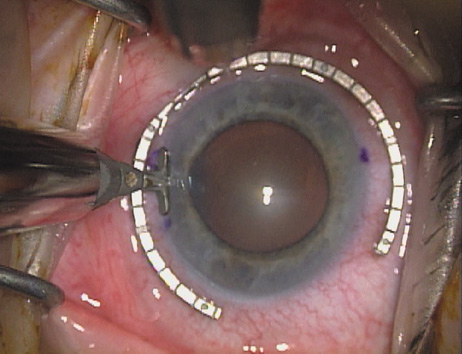

Case 1 is a 68-year-old male who presented for right cataract surgery. His refraction was −1.00 +2.25 × 80 and was recorded as reliable, consistent with his modest cataract density. Keratometry readings were 44.75 × 75 and 43.00 × 165. Corneal topography confirmed slightly more than 2.00 D of regular and slightly oblique cylinder. Consulting the nomogram, a plan was devised for a pair of LRIs to be centered over the 75-degree axis, with each incision delineating 45 degrees of arc. A single plane phaco incision was used and maintained at a size of less than 3.2 mm (Figs. 811).

Fig. 10. The single footplate diamond blade is inserted perpendicular to the corneal surface and at the peripheral most extent of clear corneal tissue. In this case, the nomogram calls for arcuate incisions of 45 degrees. Therefore, the incision is begun approximately 22.5 degrees to one side of the broad hash mark. (Reprinted from Hardten DR, Lindstrom RL, Davis EA. Phakic Intraocular Lenses: Principles and Practice. Thorofare, NJ: SLACK Incorporated, 2004, with permission.)

Fig. 11. Opposite relaxing incision is completed. (Reprinted from Hardten DR, Lindstrom RL, Davis EA. Phakic Intraocular Lenses: Principles and Practice. Thorofare, NJ: SLACK Incorporated, 2004, with permission.)